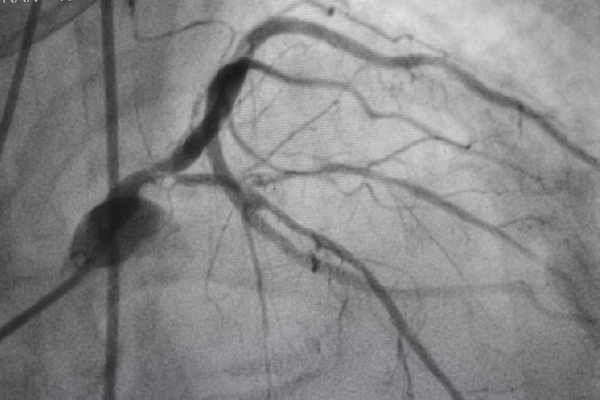

A powerful imaging technique that helps visualize the blood vessels of the brain, heart, and limbs, subtracting the surrounding “noise” (i.e., bones, tissues, and shadows)—leaving behind a crystal-clear roadmap of your circulation for prompt diagnosis and navigating towards an effective treatment for an underlying condition.

- Provides higher-quality or clearer detailed visuals of blood vessels than regular X-rays or CT scans.